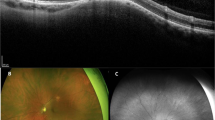

The mean follow-up duration was 68.8 ± 43.6 months (range, 6-139 months). Most lesions were solitary (92.6%), but one patient had two adjacent lesions (7.1%). Optical coherence tomography revealed that all lesions were confined to the sclera. Lesions showed mostly outer retinal abnormality, with external limiting membrane thinning or absence in 41.6% of lesions and ellipsoid layer absence in 84.6% of lesions. Most lesions showed an absence (69.2%) or thinning (23.1%) of the choroid above the lesion, and the mean choroidal thickness above the lesion for choroids with measurable thickness was 36 ± 75 μm (median, 0; range, 0–265 μm). Of 13 lesions with available follow-up data, only three lesions showed minimal growth over time.

This study demonstrates for the first time that bifocal lesions of FSN in the same eye are possible and reaffirms the relative stability of this entity.